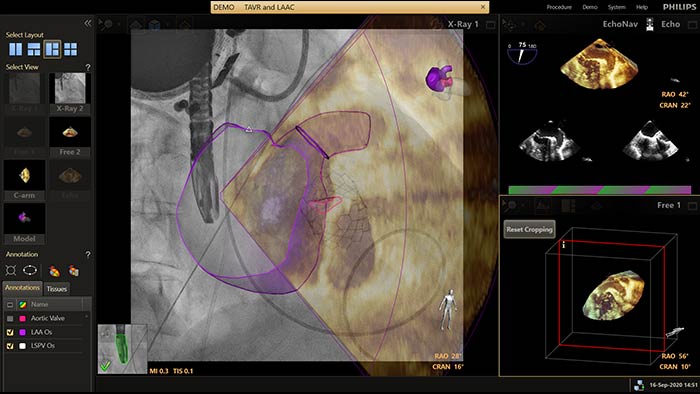

EchoNavigator reorienta y combina la información de ecografía y rayos X en una sola visualización aumentada para guiar y evaluar la relación dispositivo-tejido. En la oclusión de la orejuela izquierda (Left Atrial Appendage, LAA), EchoNavigator permite lo siguiente para aumentar la confianza y la eficiencia: